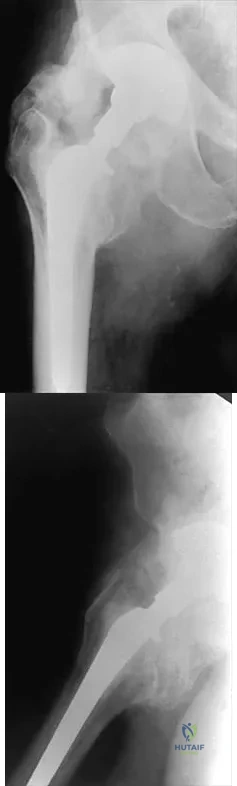

Figures 22a and 22b show the radiographs of a patient who reports stiffness of the hip and associated pain. Management should consist of

Explanation